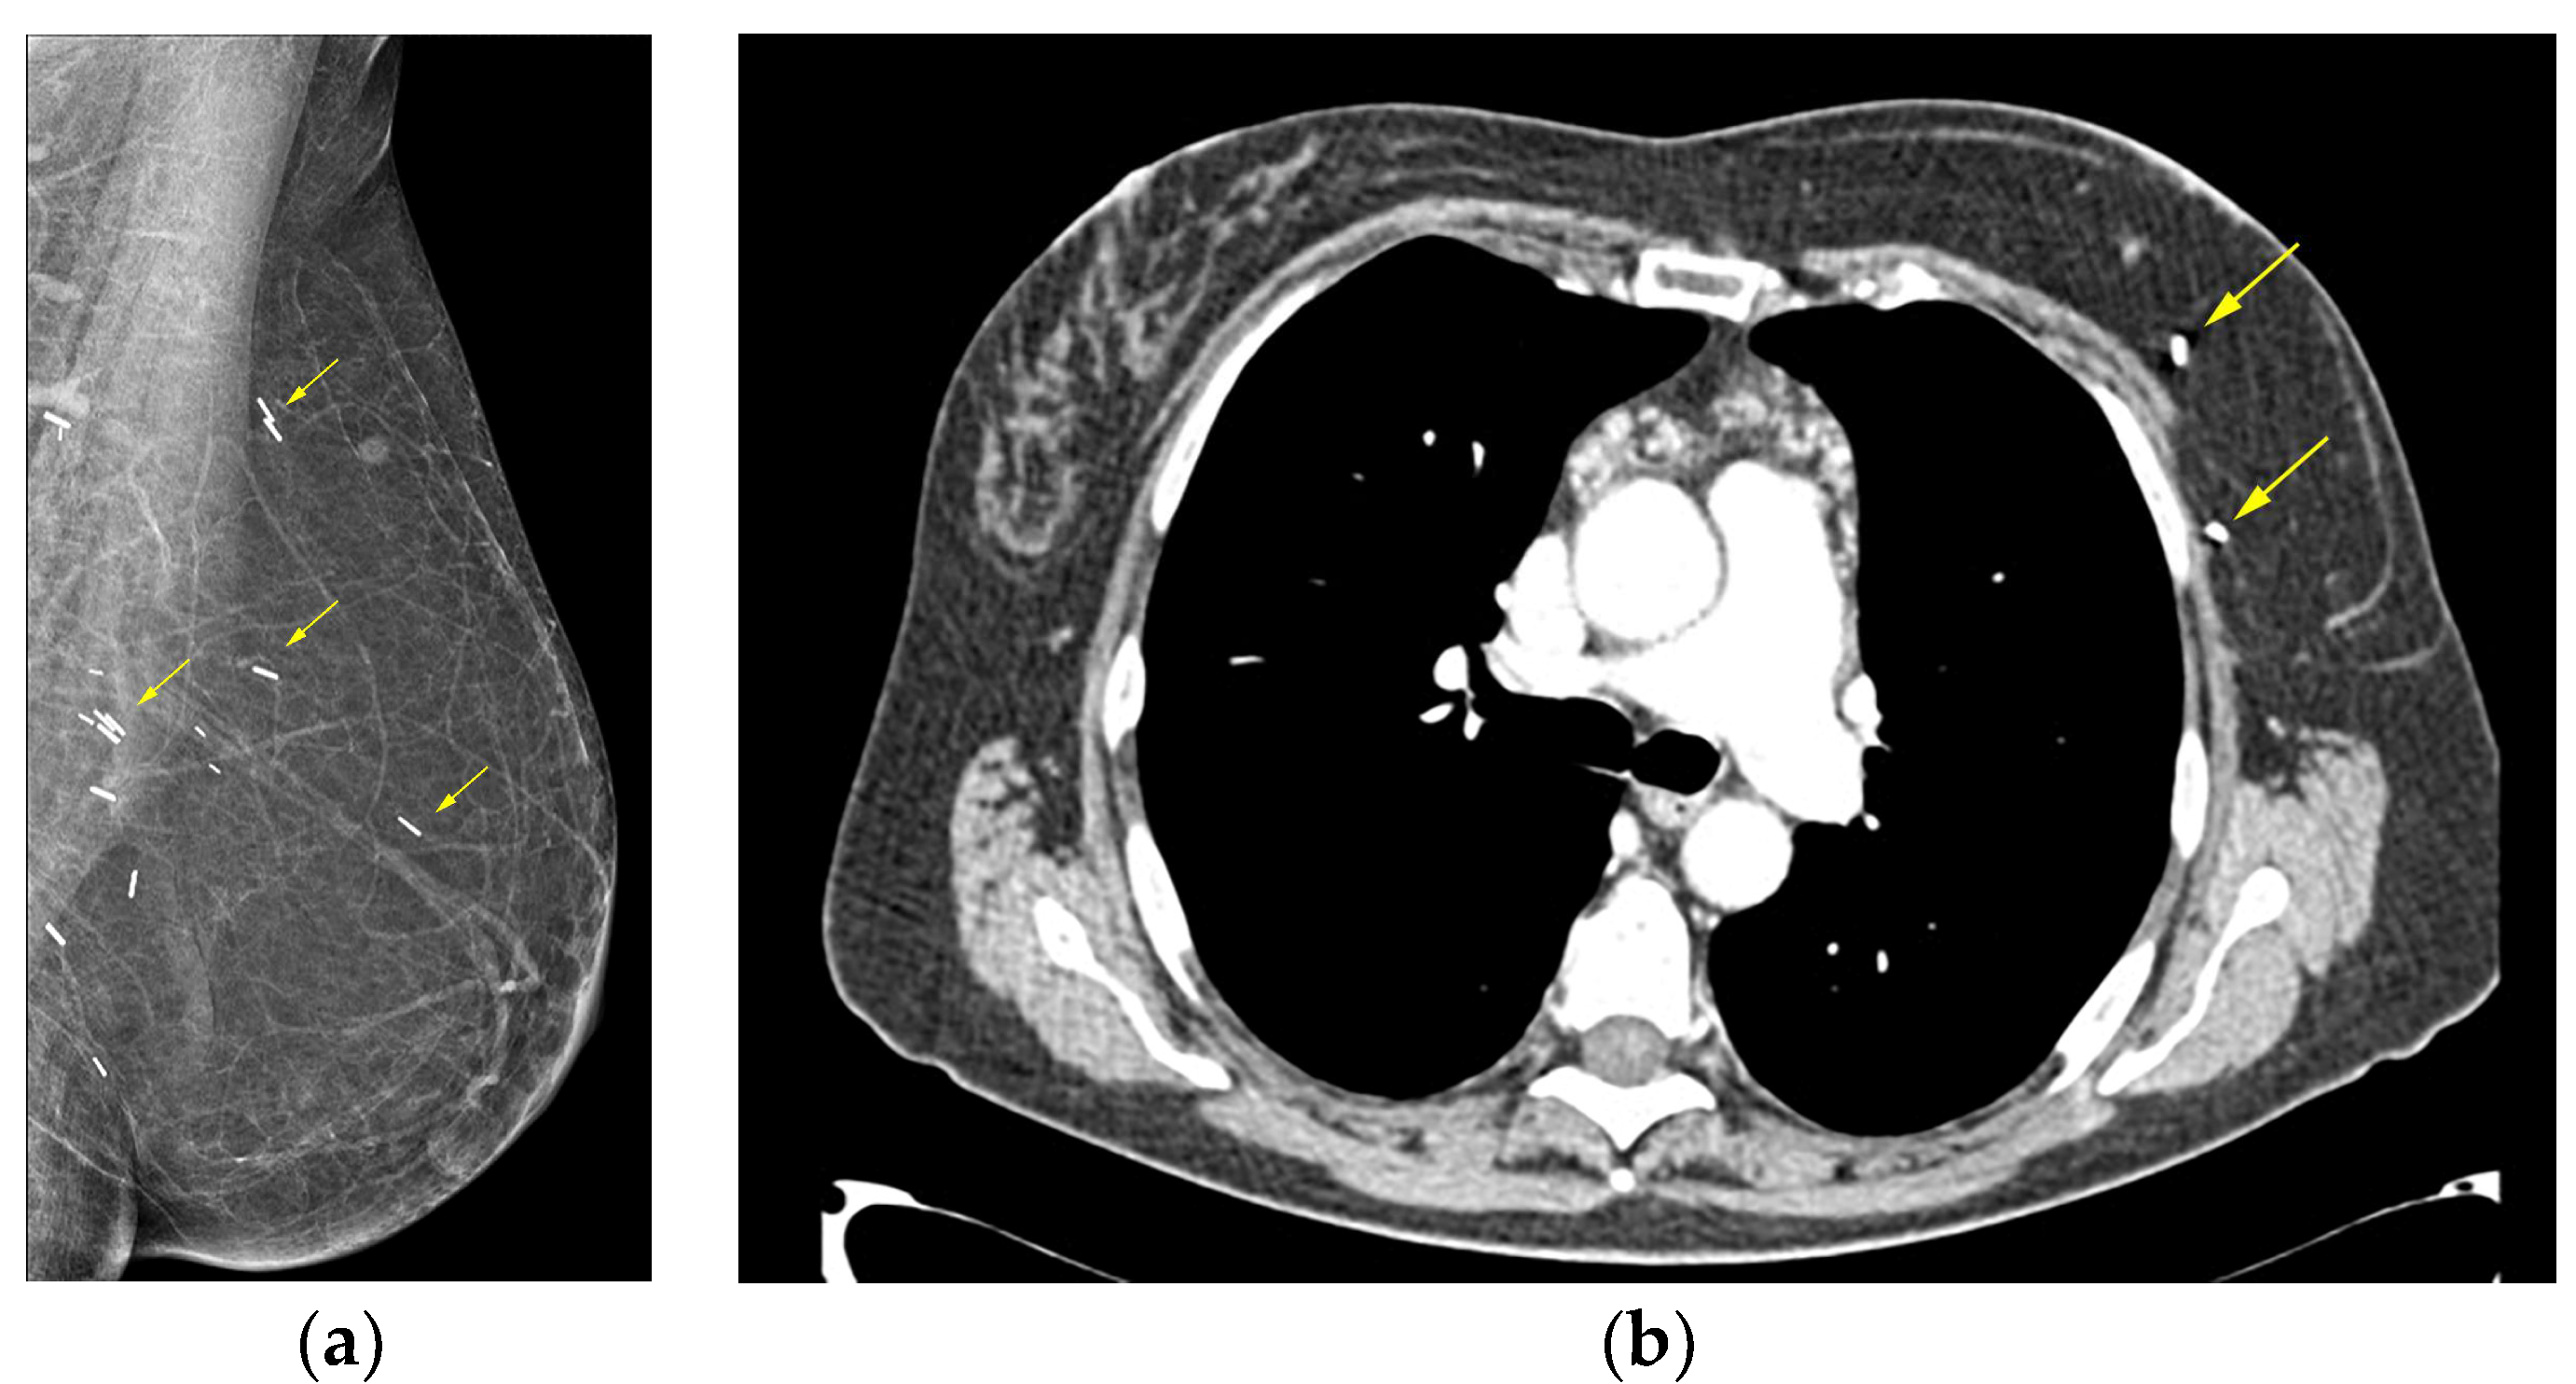

- Expert Panel on Breast, I.; Heller, S.L.; Lourenco, A.P.; Niell, B.L.; Ajkay, N.; Brown, A.; Dibble, E.H.; Didwania, A.D.; Jochelson, M.S.; Klein, K.A.; et al. ACR Appropriateness Criteria® Imaging After Mastectomy and Breast Reconstruction. J. Am. Coll. Radiol. 2020, 17, S403–S414. [Google Scholar]

- Adrada, B.E.; Karbasian, N.; Huang, M.; Rauch, G.M.; Woodtichartpreecha, P.; Whitman, G. Imaging Surveillance of the Reconstructed Breast in a Subset of Patients May Aid in Early Detection of Breast Cancer Recurrence. J. Clin. Imaging Sci. 2021, 11, 58. [Google Scholar] [CrossRef]

- Smith, D.; Sepehr, S.; Karakatsanis, A.; Strand, F.; Valachis, A. Yield of Surveillance Imaging After Mastectomy with or without Reconstruction for Patients With Prior Breast Cancer: A Systematic Review and Meta-analysis. JAMA Netw. Open 2022, 5, e2244212. [Google Scholar] [CrossRef]

- Edeiken, B.S.; Fornage, B.D.; Bedi, D.G.; Sneige, N.; Parulekar, S.G.; Pleasure, J. Recurrence in autogenous myocutaneous flap reconstruction after mastectomy for primary breast cancer: US diagnosis. Radiology 2003, 227, 542–548. [Google Scholar] [CrossRef]